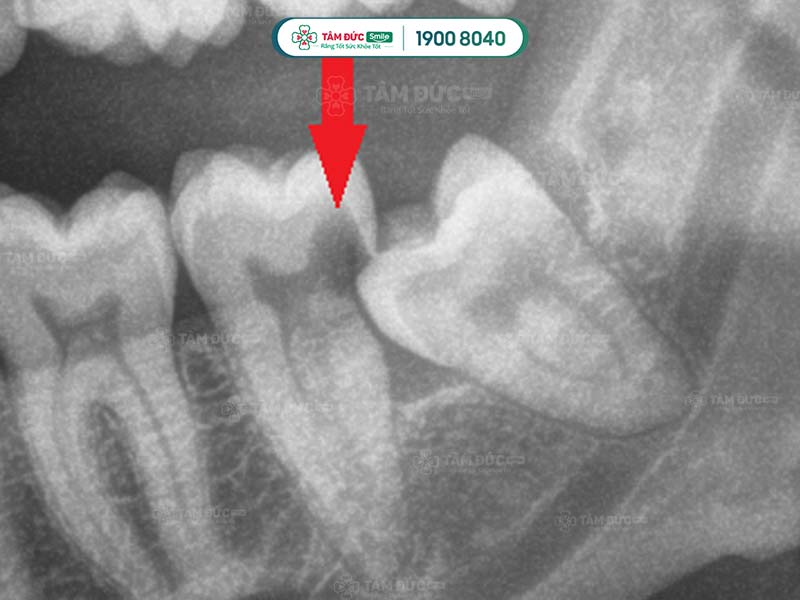

Do răng khôn không đóng vai trò quan trọng đối với cơ thể nên khi bị sâu Quý khách có thể nhổ bỏ chiếc răng khôn đó. Răng khôn mọc ngầm, mọc lệch hay mọc ngang thì cũng cần nhổ bỏ càng sớm càng tốt.

Lý do Quý khách nên chụp phim trước khi nhổ răng khôn